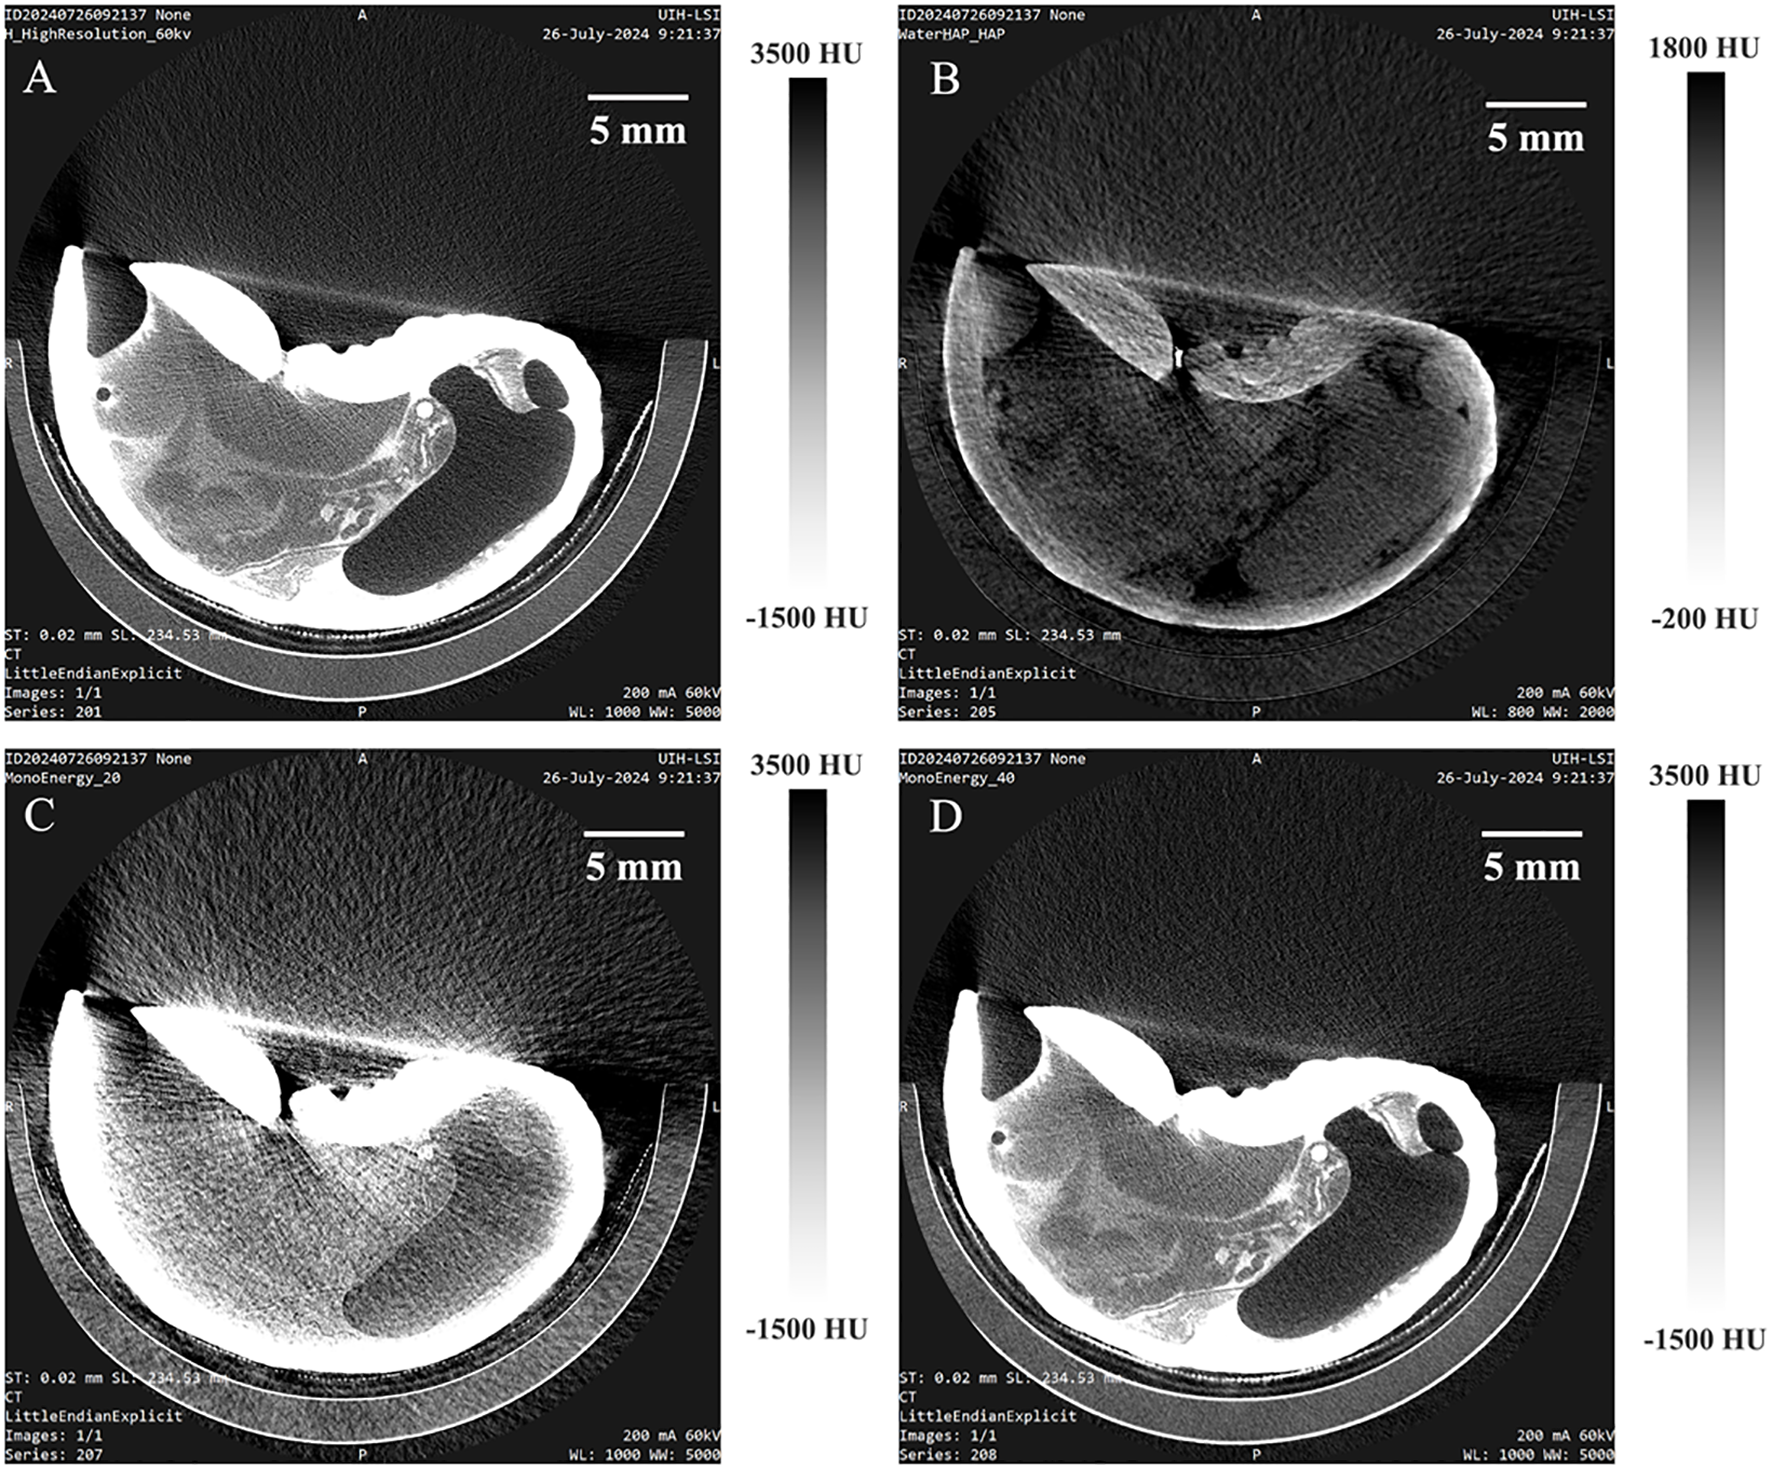

3.3 Comparison between PC micro-CT and energy-integrating detector micro-CT

To compare the imaging performance of PC micro-CT and energy-integrating detector micro-CT (EID micro-CT), the same otolith specimen was scanned using both systems, resulting in four distinct image types. The grayscale histogram of a full-energy image obtained from PC micro-CT (Figure 6A) ranged between 5215 HU and 10149 HU, with an average CT value of 7719.8 HU. Based on the image obtained from PC micro-CT, a calcium map (Figure 6B) was reconstructed, yielding an average calcium density of 1692.4 mg/ml, ranging from 1080.8 to 2629.5 mg/ml. The calcium content within the otolith gradually decreases from the periphery toward the center. Additionally, a monoenergetic image reconstructed at 100 keV (Figure 6C) ranged from 1677 to 6835.8 HU, with an average of 4427.4 HU. An image acquired using EID micro-CT (Figure 6D) ranged from 3237 HU to 14019.7 HU, with an average of 9150.3 HU. Noise levels were markedly different, with PC micro-CT showing only 512.97 HU—less than half of the 1092.10 HU observed in EID micro-CT. The reconstructed images from PC micro-CT effectively reveal the internal density variations within the otolith, whereas EID micro-CT is limited to visualizing the overall shape of the otolith without providing detailed information on density distribution.

Figure 6

CT images of Otolith under different conditions, presented from left to right: (A) full-energy image from photon-counting micro-CT, (B) calcium map derived from photon-counting micro-CT, (C) monoenergetic photon-counting micro-CT image at 100 keV, and (D) traditional integral-detector CT image. The bottom row shows the corresponding CT value histograms for each image.

Figure 8 presents the reconstructed images of Strombus canarium after immersion in a 320 mg/mL iodixanol solution for 36 hours. A calcium map and virtual monoenergetic images at 20 and 40 keV have been displayed in order. In both full-energy and high-energy virtual monoenergetic images, the shell, foot, and digestive system are clearly visible, with clear outlines of their features. The calcium map not only provides the detail structure information of the shells, but enabling quantitative study of calcium content.

Figure 8

Virtual monoenergetic imaging and calcium map results of Strombus canarium after immersion in a 320 mg/mL Iohexol solution for 36 hours, obtained using photon-counting micro-CT. The images include the full-energy image (A), calcium map (B), and monoenergetic imaging at 20 (C) and 40 (D) keV.

Material decomposition, another key spectral imaging technique, analyzes X-ray attenuation characteristics at different energy levels to separate mixed tissue signals into quantitative maps of specific base materials (e.g., water, fat, iodine). This approach enables quantitative tissue composition analysis, enhances contrast agent detection accuracy, and reduces artifact interference. Figure 6 presents a calcium map obtained via water-calcium decomposition. For fish otolith, the growth ring is the significant structure representing the aging of fish which record critical biological and environmental information (Valerio et al., 2025). Thanks to the PC micro-CT, not only can the growth ring be seen in the full-energy images, but it can be quantitatively analyzed in calcium map, offering a novel approach for studying marine organism development. Although material decomposition imaging has not yet been applied to marine biological studies, existing research has demonstrated its effectiveness in other domains. In low-energy micro-CT, material decomposition using a photon-counting X-ray detector enables the differentiation and mapping of iron, calcium, and paraffin in atherosclerotic plaques (Solem et al., 2021). In dual- and triple-energy cone-beam micro-CT, material-specific imaging allows for the separation and visualization of bone and blood vessels in ex vivo rat specimens perfused with a lead-based contrast agent (Granton et al., 2008). These applications demonstrate the potential of material decomposition for enhancing imaging contrast and specificity in complex biological structures. Further research is needed to extend this approach to marine biological studies, particularly for the quantitative analysis of biomineralized tissues.